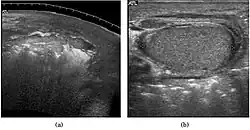

Teratoma Although teratoma is the second most common testicular tumor in children, it affects all age groups. Mature teratoma in children is often benign, but teratoma in adults, regardless of age, should be considered malignant. Teratomas are composed of all three germ cell layers, i.e. endoderm, mesoderm and ectoderm. At ultrasound, teratomas generally form well-circumscribed complex masses. Echogenic foci representing calcification, cartilage, immature bone and fibrosis are commonly seen [Fig. 5]. Cysts are also a common feature and depending on the contents of the cysts i.e. serous, mucoid or keratinous fluid, it may present as anechoic or complex structure [Fig. 6].

Fig. 5. Teratoma. A plaque-like calcification with acoustic shadow is seen in the testis.

Fig. 6. Mature cystic teratoma. (a) Composite Image. Mature cystic teratoma in a 29-year-old man. Longitudinal sonography image of the right testis shows a multilocular cystic mass. (b) Mature cystic teratoma in a 6-year-old boy. Longitudinal sonography of the right testis shows a cystic mass containing calcification with no obvious acoustic shadow.